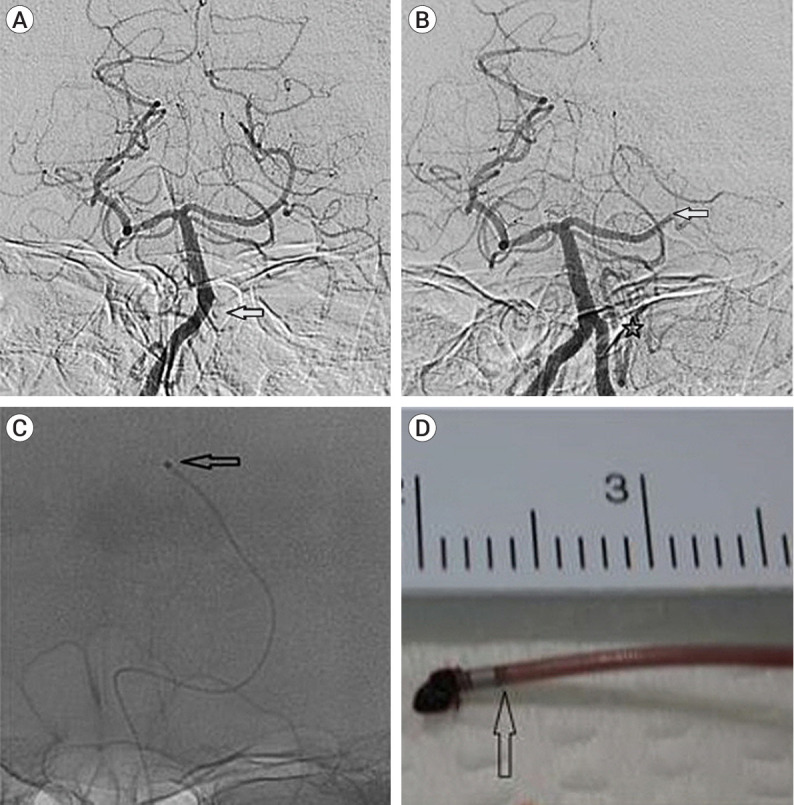

众所周知,机械血栓切除术对远端中血管闭塞(DMVO)和大血管闭塞都很有效,但迂曲的DMVO容易在支架回流血栓切除术中造成血管损伤。此外,在使用专用抽吸导管进行抽吸血栓切除术时,可能很难接触到血栓。大多数研究都描述了使用支架取栓器和专用抽吸导管治疗 DMVO 的情况,但使用微导管抽吸血栓切除术治疗 DMVO 的研究报告还很有限。在此,我们描述了三例使用微导管进行抽吸血栓切除术治疗 DMVO 的病例,随后显示出良好的效果。因此,使用微导管抽吸血栓切除术是治疗迂曲DMVO的另一种可行方法。

While mechanical thrombectomy is known to be effective for distal medium vessel occlusion (DMVO) as well as large vessel occlusion, tortuous DMVO are predisposed to vessel injury during stent retriever thrombectomy. Furthermore, getting access to the thrombus may be difficult during suction thrombectomy using a dedicated suction catheter. Most studies describe DMVO treatment using stent retrievers and dedicated suction catheters, but there are limited studies reporting DMVO treated with suction thrombectomy using a microcatheter. Herein, we describe three cases of DMVO treated with suction thrombectomy that was performed using a microcatheter and subsequently showed good results. Therefore, suction thrombectomy using a microcatheter is a viable alternative treatment for tortuous DMVO.